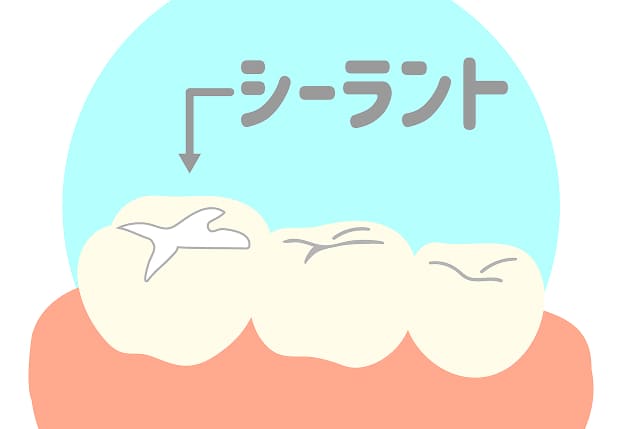

フッ素塗布、シーラントで虫歯を予防しましょう

成長段階にあるお子さまの歯は、乳歯の場合永久歯の半分の量しかエナメル質がありません。エナメル質に穴が開きやすい乳歯は虫歯になりやすい状態といえます。「乳歯は生えかわるから大丈夫」と考え、放置されてしまうケースも非常に多いですが、実は一度虫歯になってしまうと、将来生えてくる永久歯も虫歯になってしまう可能性が高くなります。

そのような状況を改善するため、当院では「フッ素塗布」と「シーラント」をおすすめしております。うまく活用して虫歯を予防していきましょう。

シーラント

むし歯になりやすい奥歯や前歯の溝をプラスチック樹脂の一種で一層埋めることで、虫歯を予防します。主に生えて間もない6歳臼歯や乳歯の奥歯に行います。